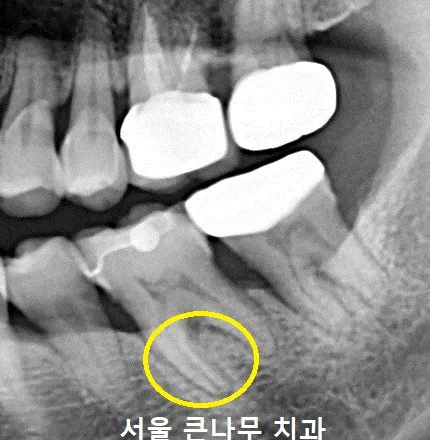

서울큰나무치과에 방문해 주신 환자분의 x-ray입니다.

치아의 뿌리 부분이 점점 진해지는 것으로 보였는데요. 치아 뿌리 끝 갈라짐이 의심되었습니다.

더 자세히 관찰하기 위해 CBCT

사진을 찍어본 결과 치아 뿌리 파절을 확실하게 관찰할 수 있었습니다. 이렇게 파절된 상태에서는 더 이상 사용할 수 없기 때문에 발치를 시행하였습니다.